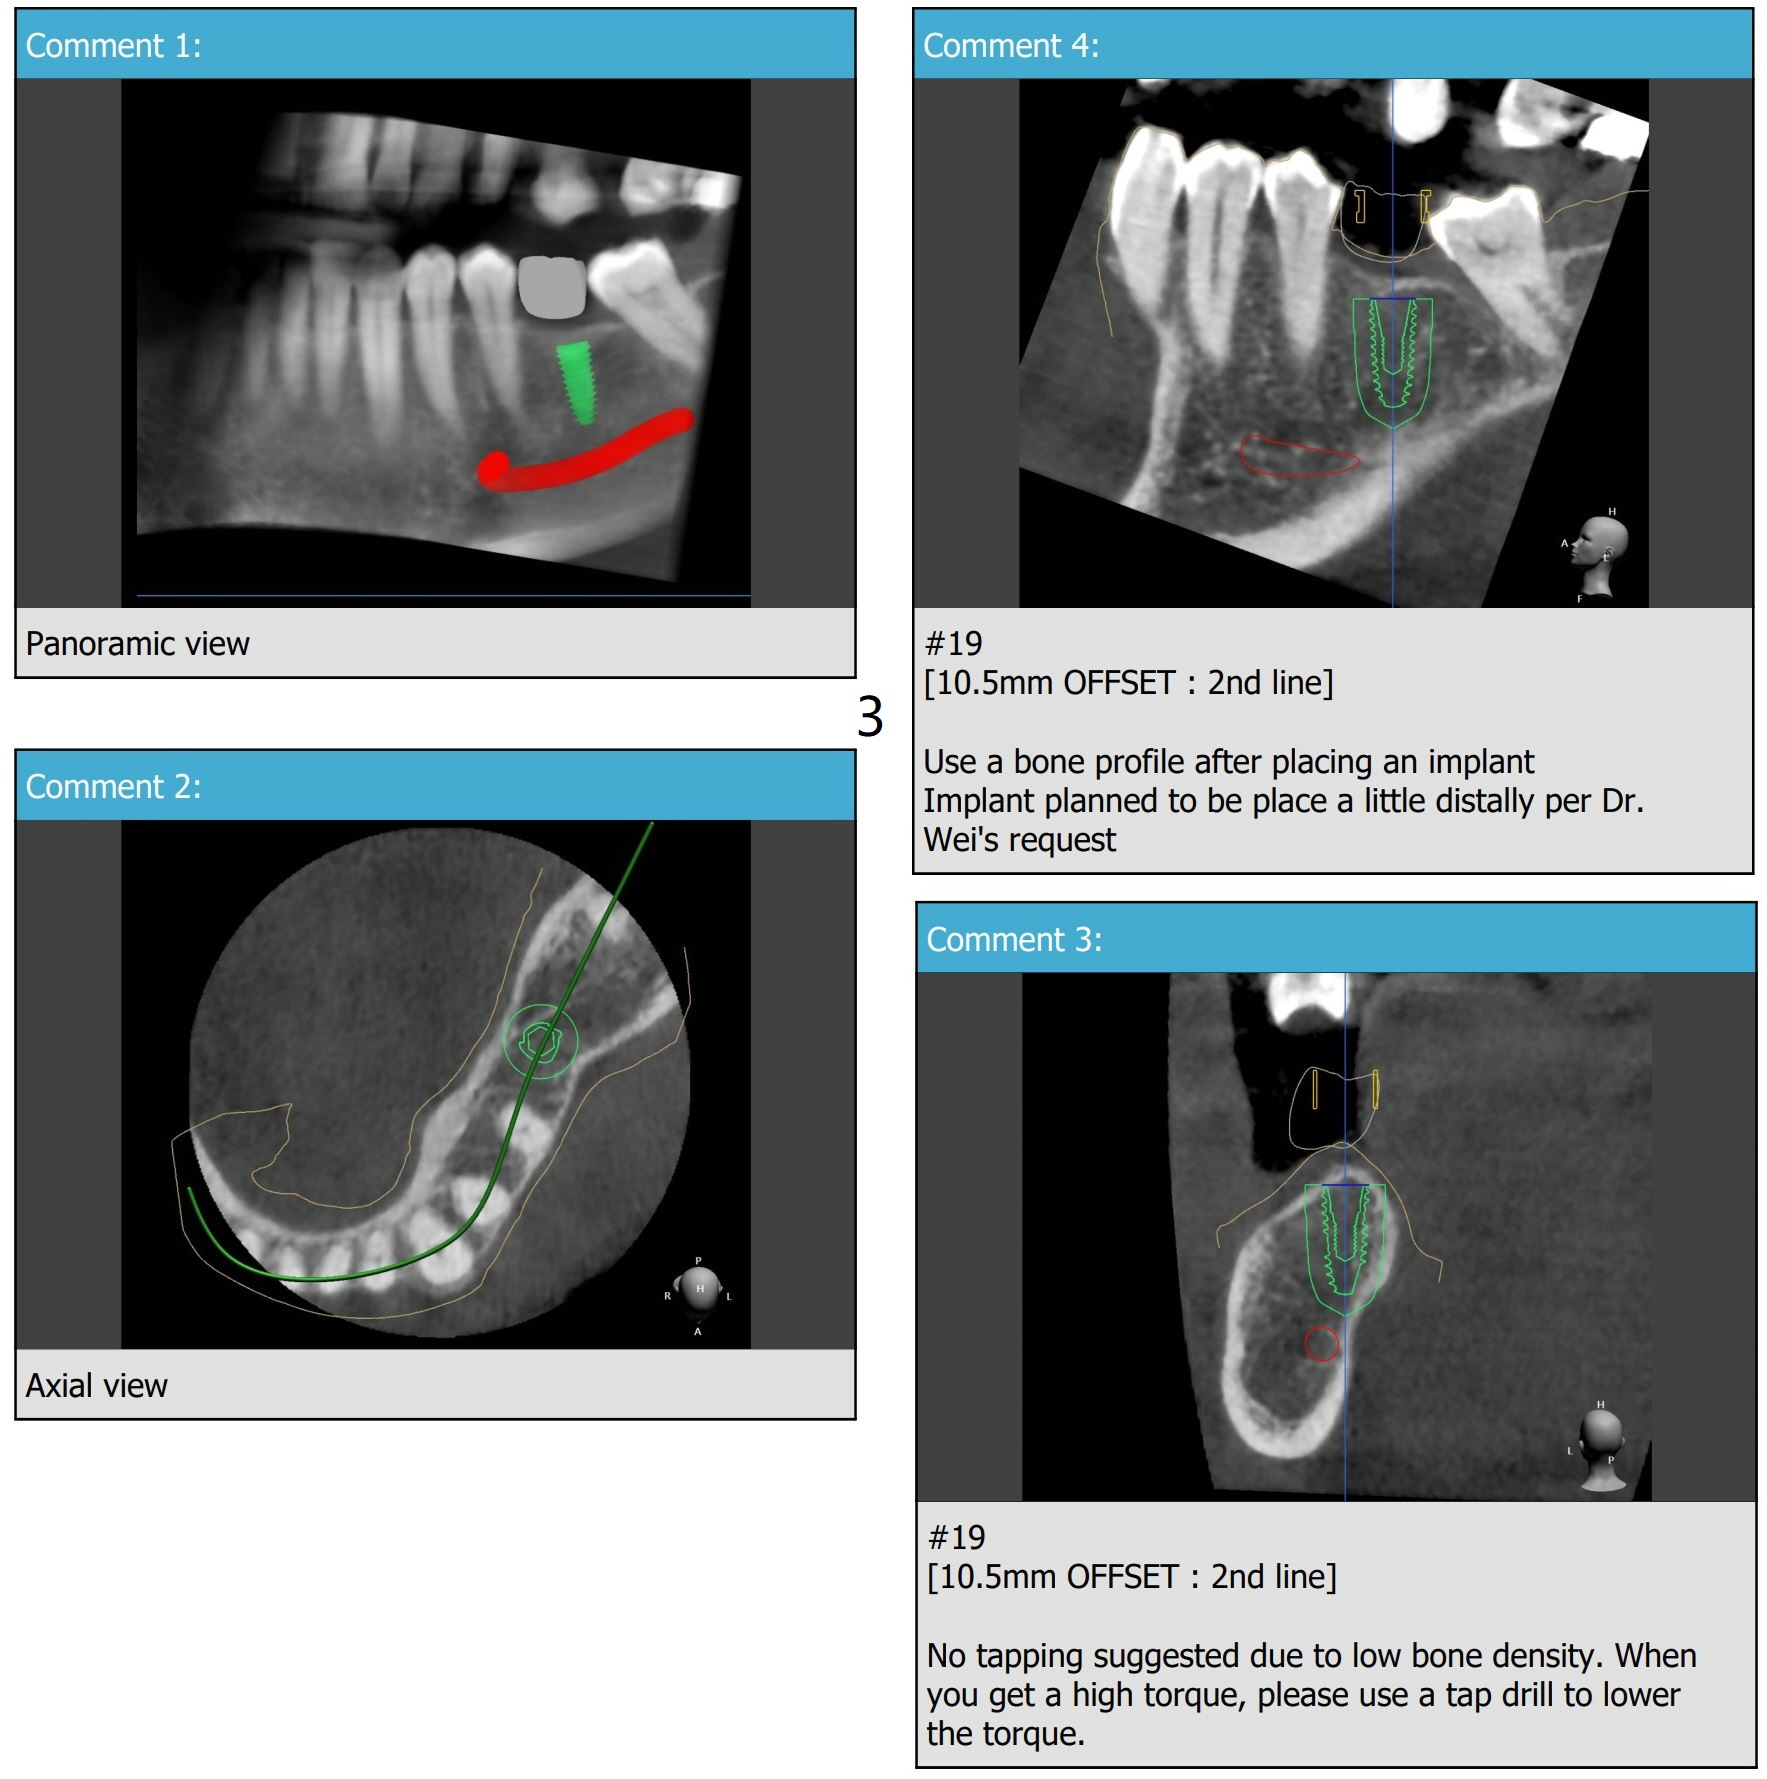

Distal Placement of Narrow Implant for Upright

A 57-year-old woman agrees to orthodontically upright #18 associated with #19 implant placement after #12 implant placement.